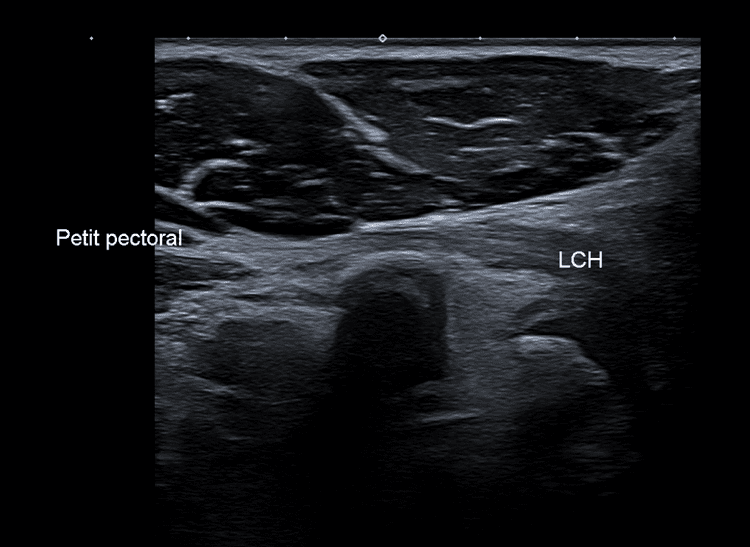

Variante anatomique du tendon du muscle petit pectoral.

US